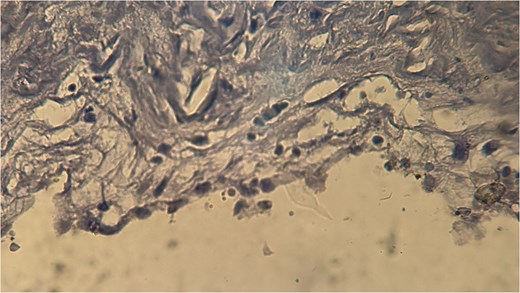

A 60-year-old Moroccan female with no significant medical history presented with chronic periumbilical pain lasting several months, without associated digestive or systemic symptoms, and preserved general condition. Clinical examination revealed periumbilical tenderness. Abdominal ultrasound was unremarkable, prompting an abdominopelvic CT scan, which identified a retroperitoneal inter-aortocaval cystic lesion measuring 86 mm. Surgical exploration revealed a large cystic mass in the mesentery of the small intestine, which was entirely excised. Histopathological examination showed variable-sized cystic cavities with a lymphatic appearance (Fig. 1), lined by flattened and regular endothelium. Some cavities contained pale eosinophilic material interspersed with lymphocytes and areas of red blood cells (Fig. 2). The interstitial tissue exhibited lymphocytic and plasmacytic inflammatory infiltrates. Immunohistochemistry confirmed the lymphatic nature with positivity for Podoplanin/D2–40 (Fig. 3) and CD34 (Fig. 4) and negativity for calretinin (Fig. 5). The patient’s postoperative course was uneventful.

Immunohistochemical staining showing positivity for podoplanin/D2–40, confirming the lymphatic origin of the lesion.